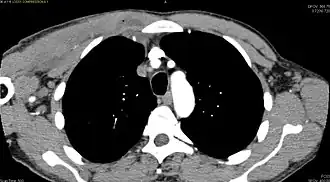

CT with IV contrast showing enlargement and heterogeneous hypodensity in the right pectoralis major muscle. A focal abscess collection with gas within it is present medially. There are enlarged axillary lymph nodes and some extension into the right hemithorax. Note the soft tissue and phlegmon surrounding the right internal mammary artery and vein. The patient was HIV+ and the pyomyositis is believed to be due to direct inoculation of the muscle related to parenteral drug abuse. The patient admitted to being a "pocket shooter" -

| Diagnostic method | Diagnostic method used for PM includes ultrasound, CT scan and MRI. Ultrasound can be helpful in showing muscular heterogeneity or a purulent collection but it is not useful during the first stage of the disease. CT scan can confirm the diagnosis before abscesses occur with enlargement of the involved muscles and hypodensity when abscess is present, terogenous attenuation and fluid collection with rim enhancement can be found. MRI is useful to assess PM and determine its localization and extension |